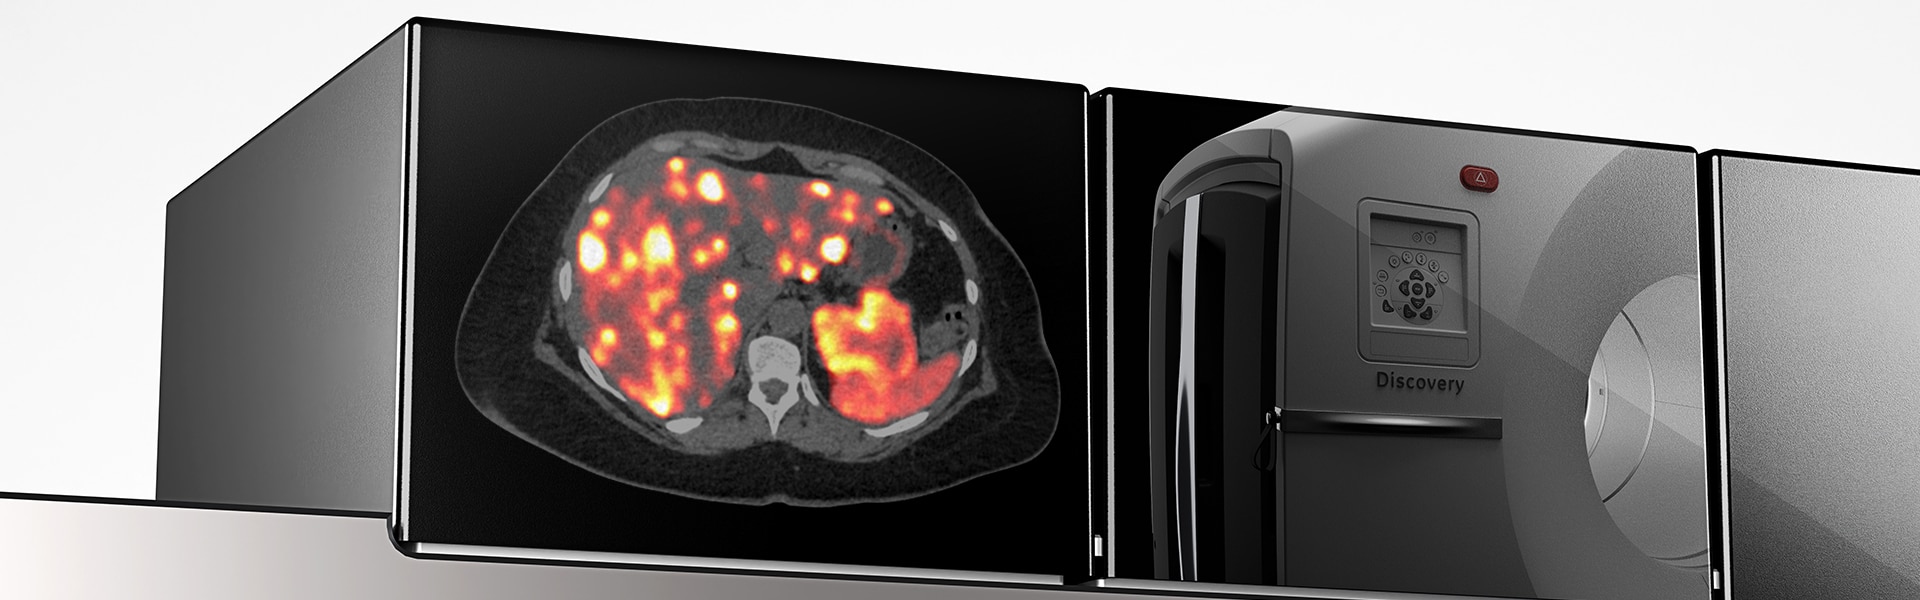

Detección digital, remasterizada

Discovery MI Gen 2 está diseñado para ofrecer

- Un campo de visión escalable

- Aumento del 50 % en el NECR máximo4

- Sensibilidad excepcional por cm (cps/kBq/cm)

- Reducción del 33 % en el tiempo de exploración4

- Una reducción del 33 % en la dosis inyectada4